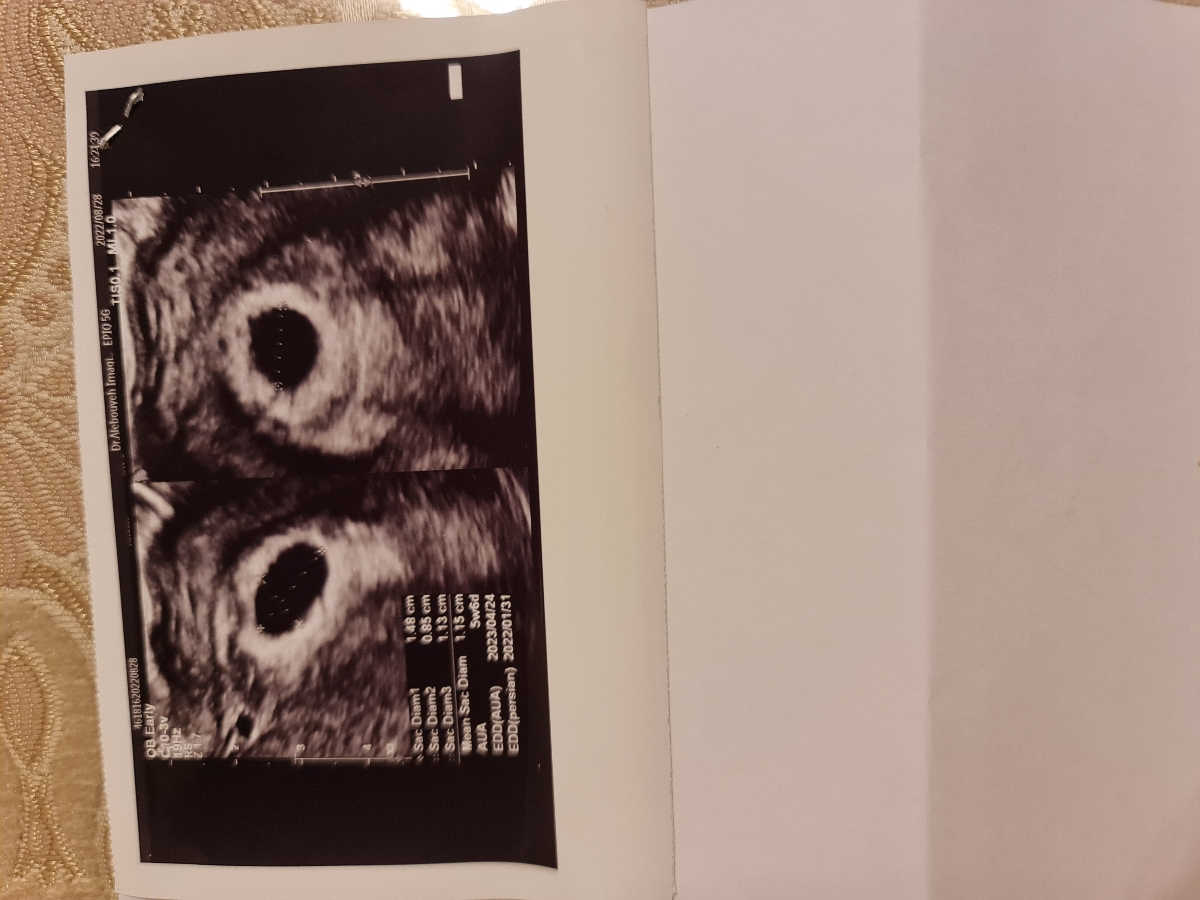

این عکس آخرین سونوی بیرونه برای ۱۰ روز پیش که خیلی معتبر هستن طبق سونوی ایشون من باید الان اول ۷ هفتگی باشم

این سونوی هفته قبلیشه

با دیدن این دو و سونو کردن خودشون دکتر گف رشد چندانی نداشته اما صبر کنی بهتره ولی خب نظر خودش این بود احتمالا باید کورتاژ کنی یا با دارو دفع کنی اگر تا هفته بعد جنین دیده نشه

خب تو ۱شهریور سونو دادی ۴ هفته و ۶ روز بودی

۶ شهریور یعنی ۵ روزبعدش سونو دادی بچه ب اندازه ۷ روز رشد کرده بوده